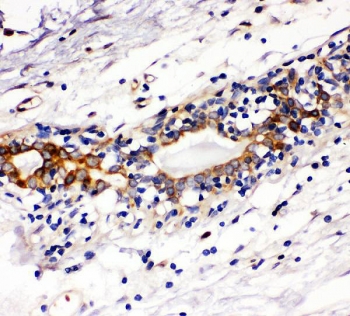

IHC staining of FFPE human breast cancer with c-Kit antibody. HIER: boil tissue sections in pH6, 10mM citrate buffer, for 20 min and allow to cool before testing.